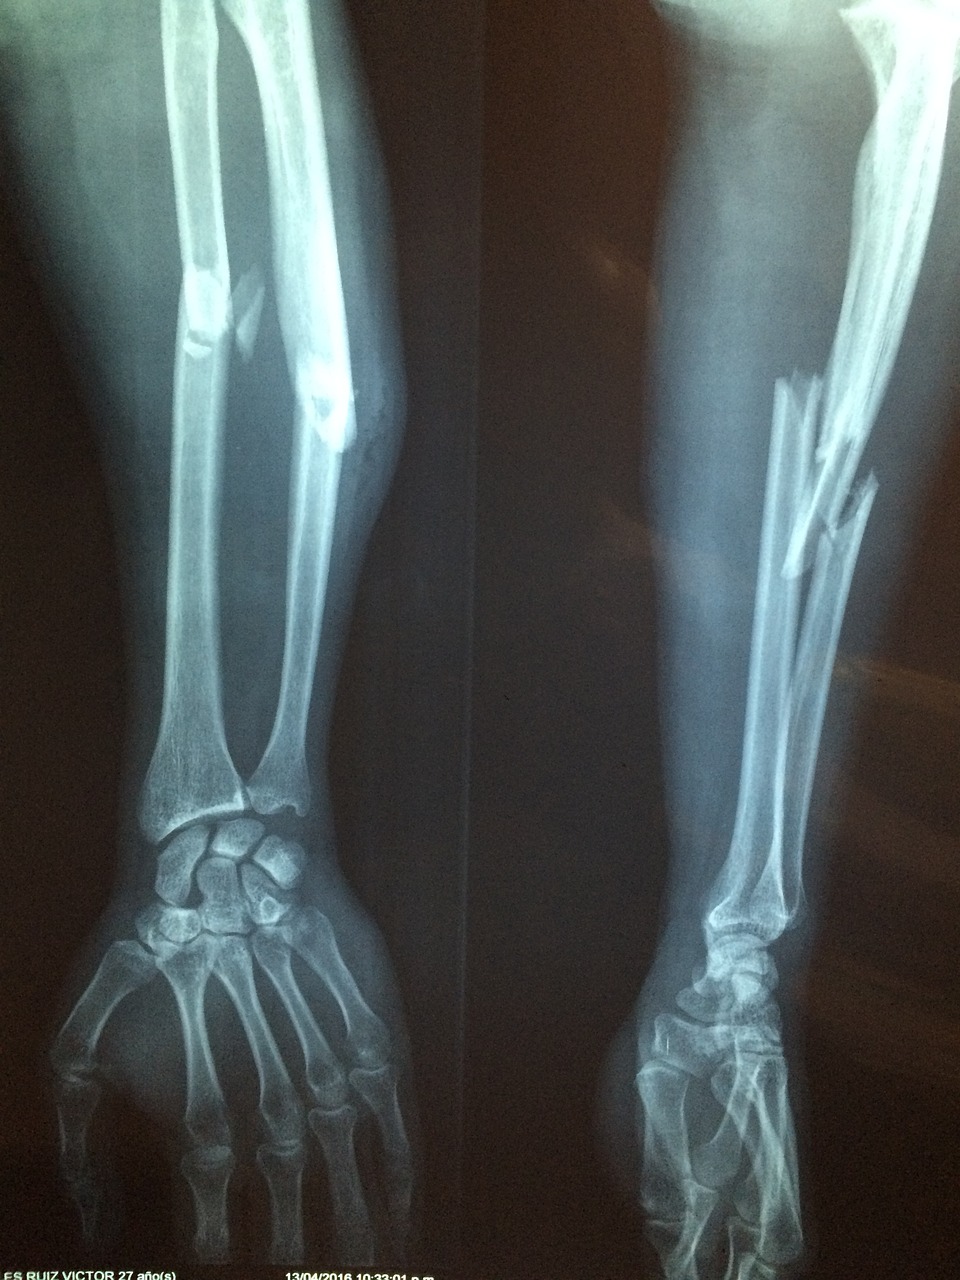

골다공증은 뼈 골절이 발생할 때까지 눈에 띄는 증상 없이 진행되기 때문에 흔히 '침묵의 병'이라고도 불리는 질환입니다. 이 상태를 이해하고 예방조치를 취하는 것은 평생 동안 건강한 뼈를 유지하는 데 도움을 줄 수 있습니다. 먼저 골다공증이란 뼈 밀도가 감소하고 뼈조직이 약해져서 골절의 위험이 증가하는 골격 질환입니다. 이 질환은 뼛속 구조가 부러지는 것이 아니라 뼈조직의 밀도가 떨어짐으로 부러지기 쉬운 상태를 말합니다. 뼈는 자연스럽게 오래된 뼈가 새로운 뼈조직으로 대체되면서 지속적으로 이런 과정을 거칩니다. 하지만 골다공증을 앓음으로써 이 균형은 시간이 지남에 따라 순골량의 손실을 야기하면서 방해를 받습니다. 이 질환은 노인, 폐경기 이후의 여성들에게 걸릴 가능성이 더 높으며, 특정한 위험 요소를 가진 젊은 개인들에게도 영향을 미칠 수 있습니다. 그렇다고 폐경이 골다공증을 불러일으키는 것은 아니며 그전에 올 수 있어 뼈 상태를 정기적으로 알아보는 것이 중요합니다.

골다공증 일반적인 증상으로는 다음과 같습니다. 먼저, 허리나 등에서 일어나는 급성이나 만성적인 통증이 있습니다. 또한, 경추 디스크와 함께 일어나는 경우가 많으며 뼈의 조직이 약해져서 무게감이 생기거나, 몸을 움직일 때 뼈에서 작은 소리가 들릴 수 있습니다. 여성이 이 질환을 앓는다면, 그것은 자신의 호르몬 변화와 밀접한 연관이 있을 수 있습니다. 이 대사변화가 골의 손상에 영향을 미치며 생리주기가 불규칙하거나 조기 폐경이 발생할 수 있습니다. 허리나 골반, 손목 등과 같은 곳에서 반복적인 골절이 일어나는 것도 증상 중 하나입니다. 이런 증상이 있다면 무시하지 말고 병원에 가서 진료를 받아보시는 게 좋습니다. 골다공증을 예방하는 것은 규칙적인 운동과 함께 칼슘과 비타민D가 풍부한 균형 잡힌 식사를 통해 유년기와 청소년기 동안 튼튼한 뼈를 만드는 것에서부터 시작됩니다. 걷기나 근력운동으로 골밀도를 유지하는데 도움을 줄 수 있으며, 노인의 경우에는 건강한 생활습관을 가지고, 낙상 예방법을 알고 있어야 합니다. 또한, 정기적인 골밀도 검사도 필요합니다. 골다공증의 치료로는 골감소를 늦추고, 골밀도를 높이는데 집중합니다. 예방법으로는 칼슘과 비타민 D 외에 골밀도 감소를 방지하고 골강도 증가에 도움을 주는 규칙적인 운동이 있습니다. 예로는 근력운동, 요가, 유산소 운동 등이 있습니다. 또한, 금주와 금연을 하는 것입니다. 담배와 술은 뼈 건강에 악영향을 주기 때문에 되도록이면 중단하는 것을 추천합니다. 볼 때는 쉬울 수 있지만, 막상 실천하기에는 시간이 부족하기도 하고, 지속적으로 해야 하기 때문에 어려움을 겪을 수 있습니다. 하지만 자신의 뼈 건강을 위해 노력해 주셨으면 좋겠습니다.